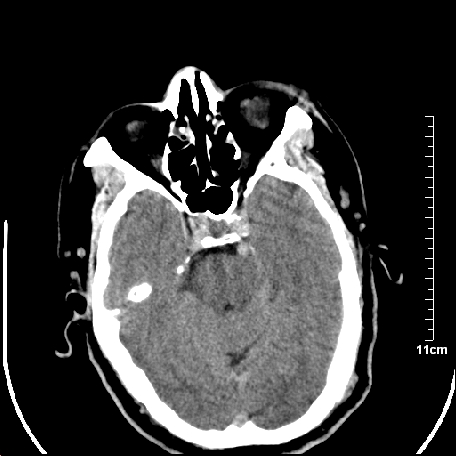

外伤患者,什么病,

外伤患者,没什么症状,

颅内未见明显创伤性影像,建议上传骨窗,看看左侧颧弓

双侧外侧裂,左侧脑沟见高密度结节影,边清,还有鞍上池层面密度也高

都是血管。

脑血管硬化?高血红蛋白症?

2.老年脑,基底动脉硬化迂曲。

基底动脉硬化迂曲。高血红蛋白血症。